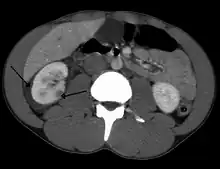

Traumatisme abdominal résultant en la contusion du rein droit (flèche vide) et du sang entourant le rein en question (flèche pleine).